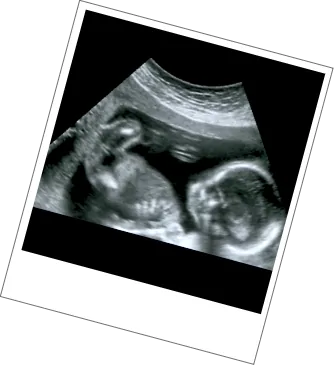

11-14 Weeks

The first ultrasound scan you receive from the NHS is to estimate the due date of your baby. The timeline for this scan depends on where in the UK you are based. You should be offered this scan between 11 to 14 weeks.

This scan can include screenings to test for Down’s syndrome, Edwards’ syndrome and Patau’s syndrome, though these screenings are optional. If you miss the window for this, our NIPT blood screening is available from 10 weeks.